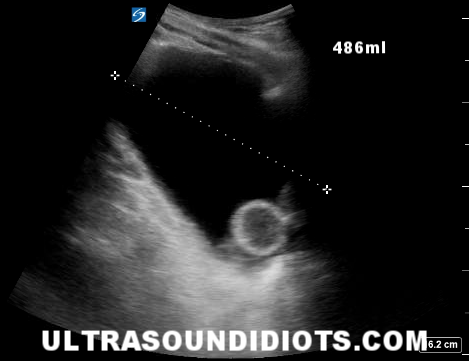

EFAST Pelvic Exams